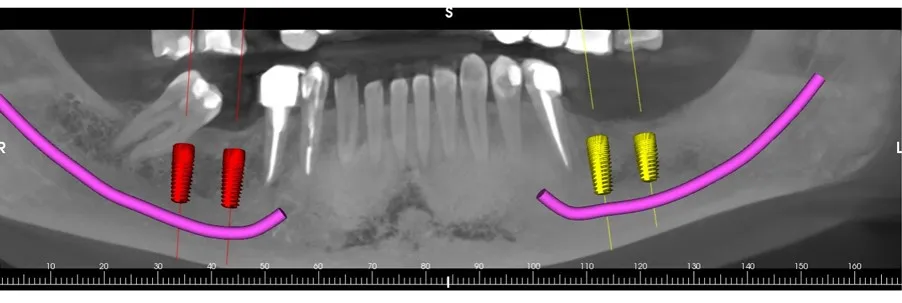

Dual Arch Rehabilitation — All-on-4 & All-on-6

Complete upper and lower jaw rehabilitation. All-on-4 concept for maxilla and All-on-6 for mandible with custom surgical guides.